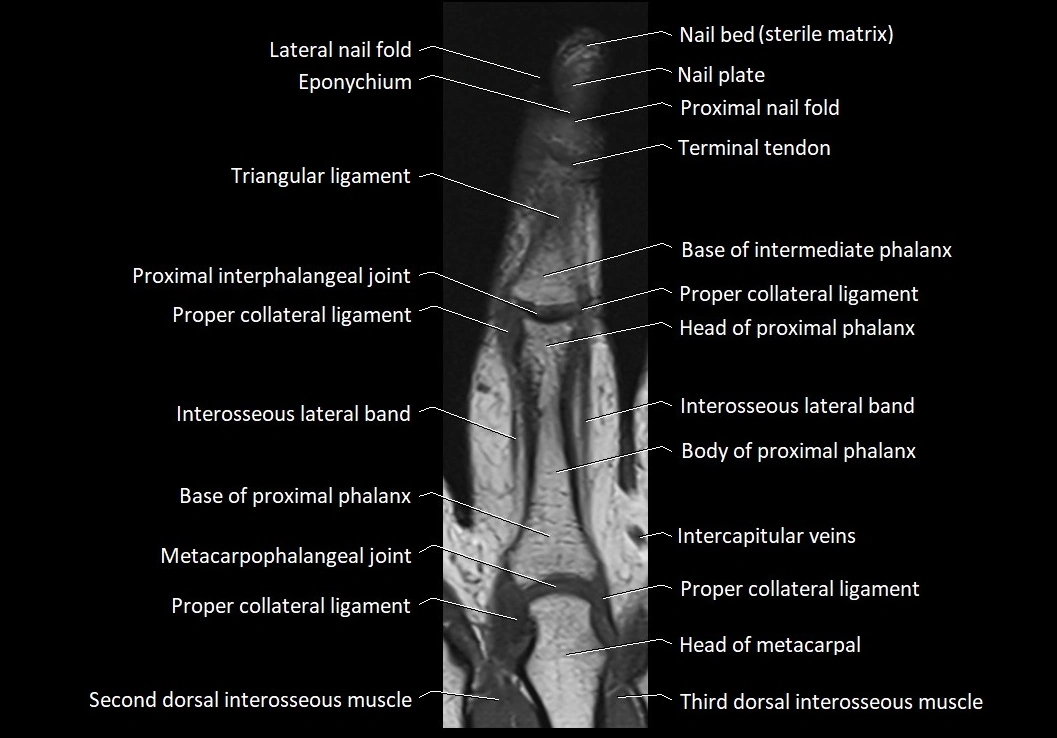

MRI images